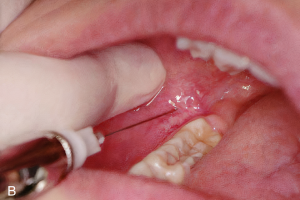

Сенсорная иннервация верхней челюсти обеспечивается второй ветвью тройничного нерва - верхнечелюстным нервом. Эта ветвь покидает полость черепа через круглое отверстие, достигает крылонебной ямки и проходит сквозь нее, как подглазничный нерв, отдавая множество ветвей. Что касается местной анестезии на верхней челюсти, важны следующие ветви:

- Большие и малые небные нервы

- Задние, средние и передние верхние альвеолярные нервы

- Подглазничный нерв (Рис.1)

Рисунок 1. Ход верхнечелюстного нерва и его главных ветвей.